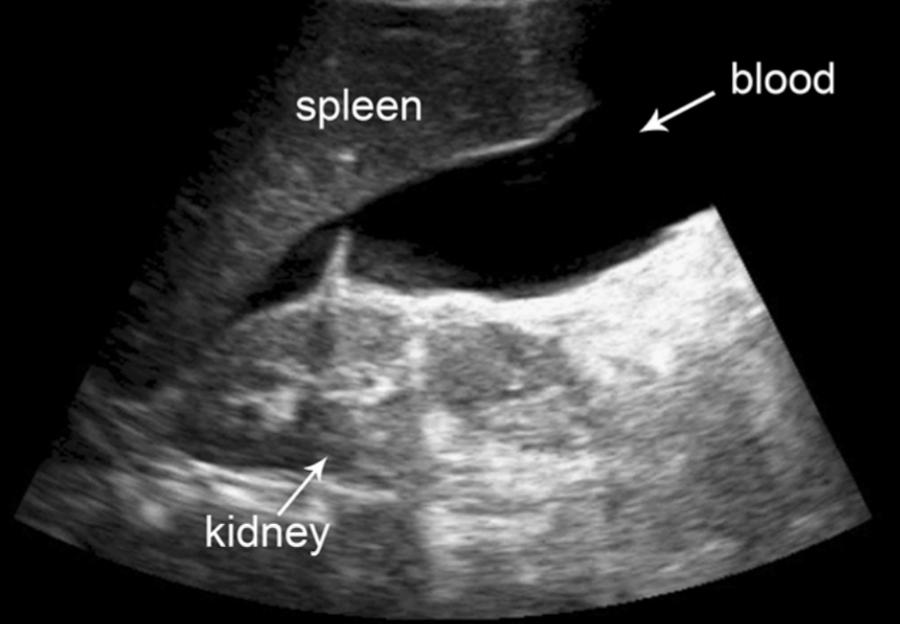

Nuestra institución tiene su área de influencia en toda la zona norte de Manabí, con amplias áreas rurales y urbanas, una de sus principales actividades económicas es el comercio basado en la agricultura, pesca, entre otros, exponiendo a la población a muchos accidentes relacionados a estas actividades, así mismo, no solo a nivel local, sino nacional e internacional aumentan las lesiones y muertes por accidentes de tránsito. Desprende de este argumento la realización del TALLER de ECOFAST, herramienta de apoyo diagnostico importante en el área de EMERGENCIAS en cuanto a toma de decisiones en pacientes que arriban a nuestra institución con traumatismos toracoabdominal cerrado en estado de shock hipovolémico de causa no filiada, considerando que este procedimiento es una herramienta accesible, portátil, no invasiva, reproducible y confiable para el diagnóstico de presencia o ausencia de líquido libre en cavidad abdominal, pleural o pericárdica, según los resultados obtenidos por las diferentes técnica se deciden procedimientos sea quirúrgicos o mini invasivos, se realiza este taller para generar destrezas y agilidades en nuestro personal constituido por Médicos Generales Asistenciales y Médicos Internos Rotativos.